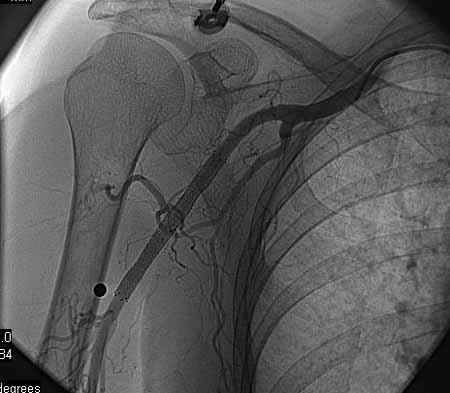

标题: DSA0091:肱动脉支架 [打印本页]

标题: DSA0091:肱动脉支架

女,66岁,右上肢无力.

图象清晰,做的很漂亮